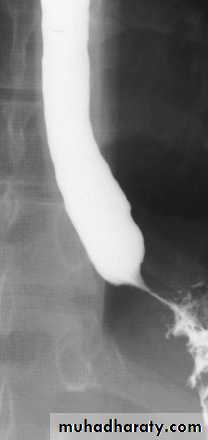

It is a neuromuscular abnormality result from failure of relaxation of the cardiac sphincter, which present at barium examination as a smooth , tapered narrowing always at the lower end of esophagus (bird beak or rat-tail appearance).There is associated dilatation of the esophagus, which often shows absent peristalsis. The dilated esophagus usually contains food residues and may be visible on CXR. The lungs may show consolidation and bronchiectasis from aspiration of the esophageal contents. The stomach gas bubble is usually absent.